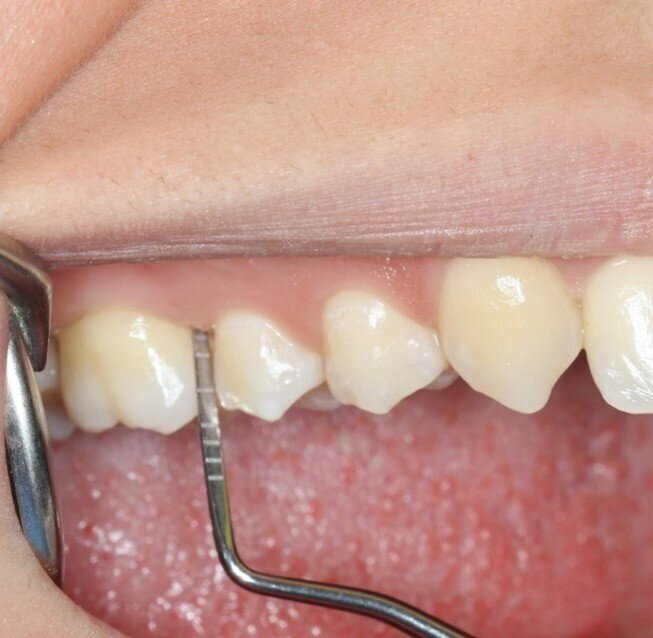

A una settimana dall’applicazione, i pazienti riferiscono una riduzione significativa di sanguinamento e sensibilità gengivale, con risultati superiori rispetto alla sola pulizia professionale. Nei casi di gengivite e tasche parodontali fino a 3 mm, UBIGEL INPERIO ha dimostrato di favorire una parziale o completa regressione dell’infiammazione, contribuendo al ripristino dell’attacco epiteliale e all’eliminazione del sanguinamento grazie alla sua azione antibatterica mirata. Nella Figura 1 è mostrata la situazione iniziale del paziente prima del trattamento.Dopo una settimana dall’applicazione di Ubigel Inperio (Fig. 2), si osservano i primi miglioramenti clinici. Il sondaggio pre-trattamento, effettuato sette giorni dopo l’igiene professionale, evidenziava una profondità di 3 mm con presenza di sanguinamento gengivale (Fig. 3). A distanza di 21 giorni dal trattamento, il sondaggio mostra una profondità della tasca inferiore a 2 mm e l’assenza di sanguinamento, segno di un netto miglioramento dello stato gengivale (Fig. 4).